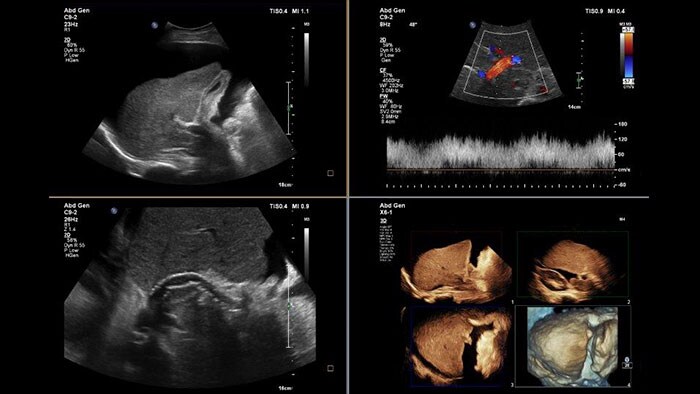

Perform advanced visualization and quantification of ultrasound volume

US Q-App General Imaging 3D Quantification (GI3DQ) provides advanced viewing, manipulation, and quantification of 3D data sets. Perform advanced functions such as MPR interrogation, iSlice tomographic imaging, and volume rendering as well as volumetric measurements using multiple methods including semi-automated tools. Results generated from this tool can be appended to the patient’s exam for complete documentation.